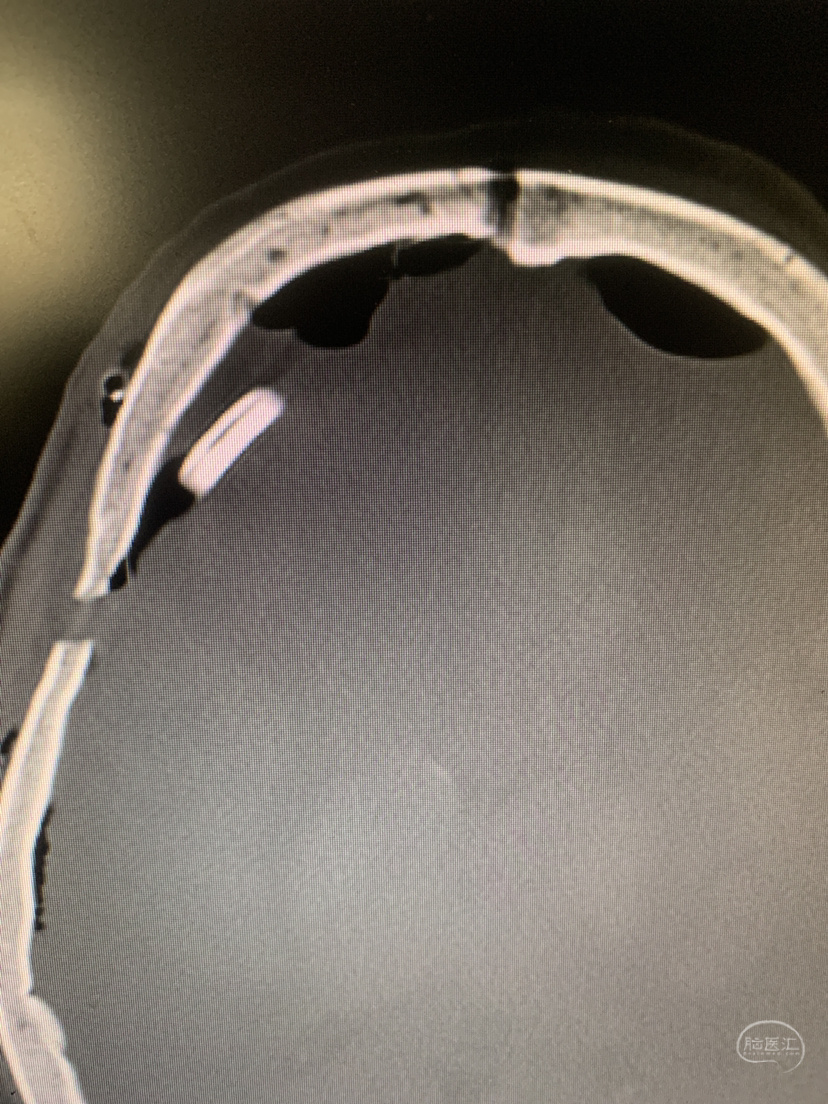

双侧入路计划(为降低优势半球损伤风险先右侧处理,实在不好搞再左侧)

从右额分块切除处理大部分后,因条件所限单侧入路风险高遂加开左侧额外侧(骨窗较右侧小)。